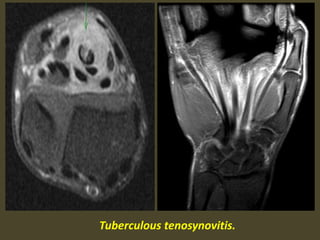

Tuberculous tenosynovitis.